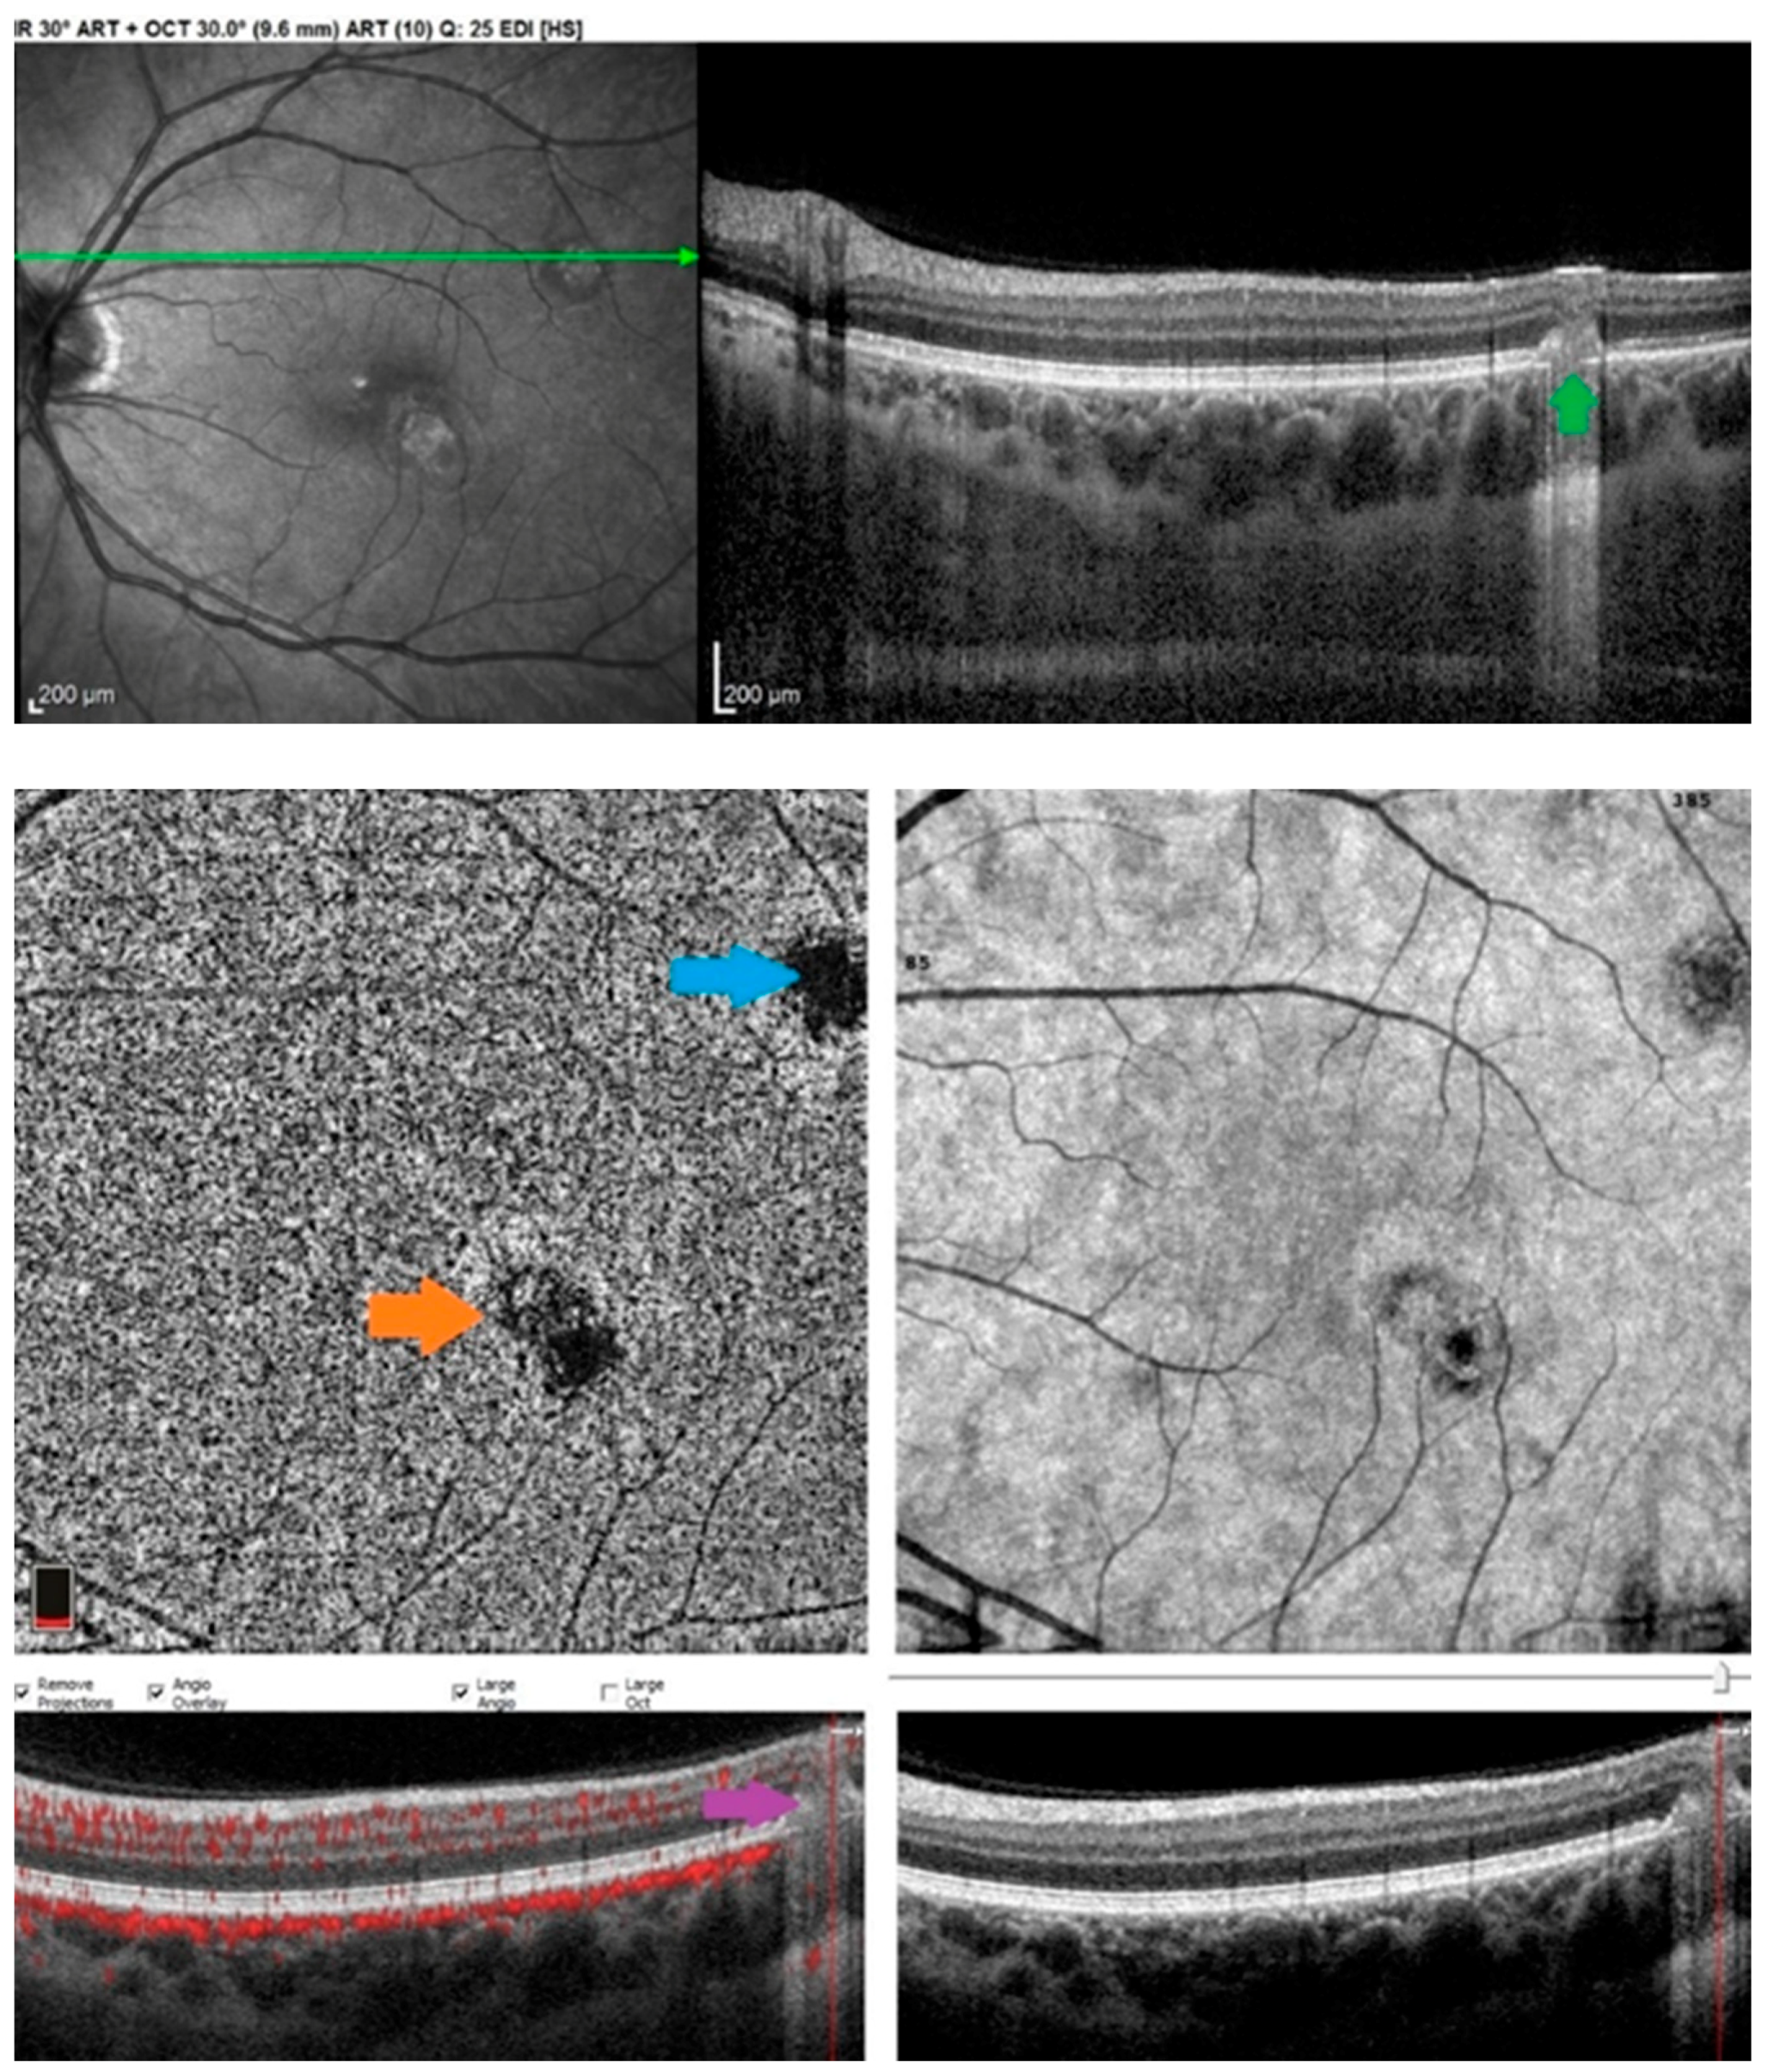

- El Ameen, A.; Herbort, C.P. serpiginous choroiditis imaged by optical coherence tomography angiography. Retin. Cases Brief Rep. 2018, 12, 279–285. [Google Scholar] [CrossRef]